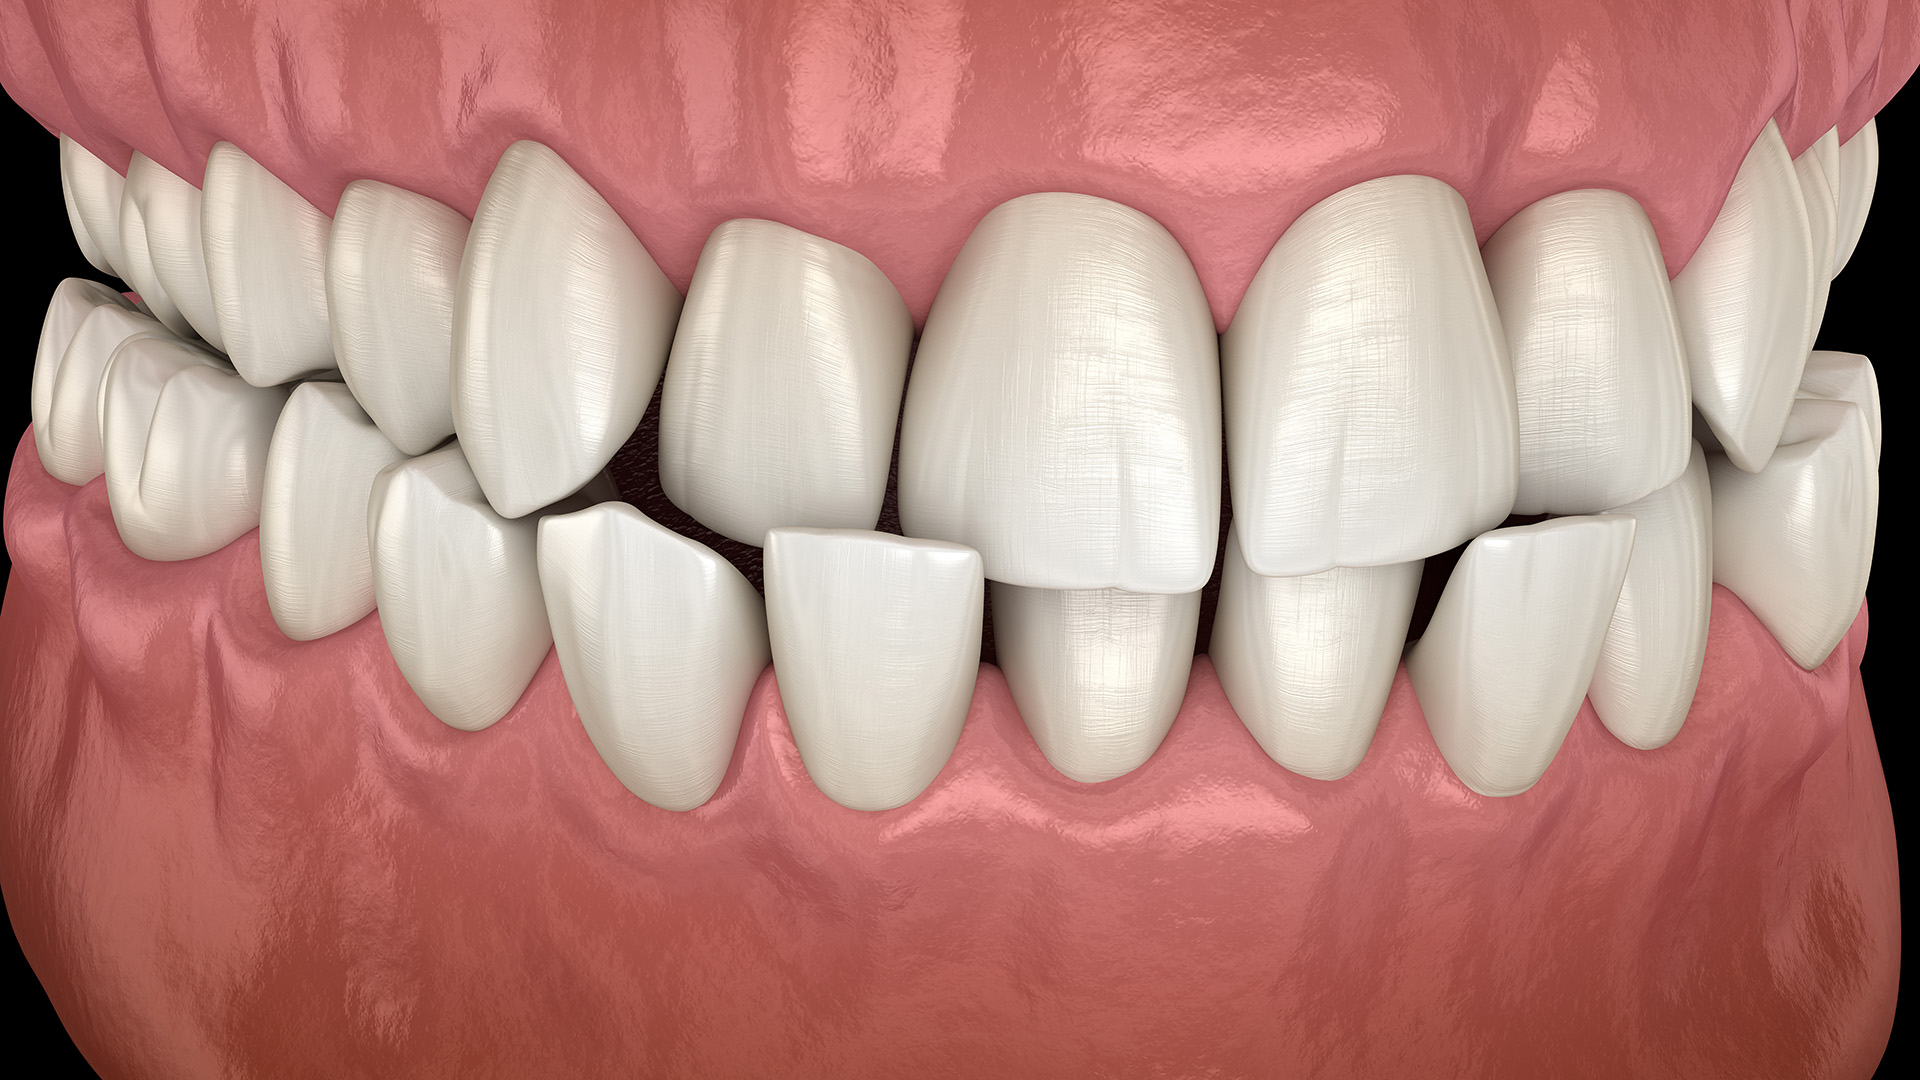

Съдържание Какво представлява обратната захапка? Обратната захапка е състояние, при което долните предни зъби се показват пред горните предни зъби. Това се получава, когато долната челюст излиза пред горната челюст. Обратната захапка е малоклузия (неправилно подредени зъби) от клас III. При по-тежки случаи обратната захапка може дори да повлияе на външния вид. Колко често срещана […]